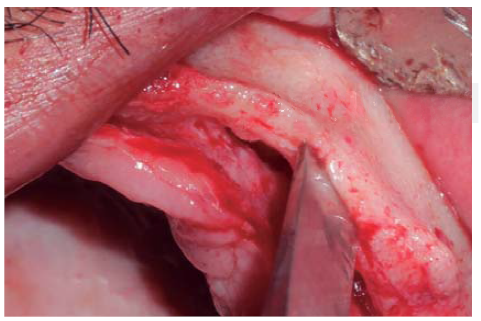

Se realizó una incisión supracrestal a espesor total, elevación del colgajo mucoperióstico exponiendo la tabla ósea hasta 4 mm de la cima de la cresta hacia vestibular y desde ese punto se dividió el colgajo a espesor parcial (Figura 3). Luego se marcaron los puntos de impacto en los sitios designados según la guía quirúrgica para la colocación de los implantes y se iniciaron las perforaciones con una fresa de 1.6 mm de diámetro para determinar el eje y profundidad deseada para los implantes. Luego se procedió a crear un surco a nivel crestal con un disco de diamante rompiendo el hueso cortical para crear el acceso a los escoplos al hueso esponjoso y con éstos se procede a separar las tablas óseas hasta llegar a una profundidad de 5 mm (Figuras 4 y 5). Seguidamente, se continuaron las perforaciones con una fresa de 2.0 mm de diámetro (Figura 6) y se realizó la expansión de la tabla vestibular creando una fractura en tallo verde con los expansores hasta alcanzar el diámetro del lecho óseo suficiente para poder utilizar la última fresa de 3.2 mm de diámetro (Figuras 7 y 8). Posteriormente, se colocaron los implantes a una velocidad de 25 rpm y a un torque de 35 Ncm (Figuras 9 y 10). Seguido de esto, se colocó un injerto óseo bovino particulado (Bonefill® Bionnovation Biomedical, Sao Paulo-Brazil), con la finalidad de preservar la integridad de las tablas óseas vestibulares (Figura 11). Todos estos procedimientos, se realizaron de la misma manera para la colocación de los seis implantes. Finalmente, se suturó con nylon monofilamento 5/0.

Figura 5 Cincel óseo ingresando a la porción medular, separando el reborde cortical llevando a una fractura en tallo verde.